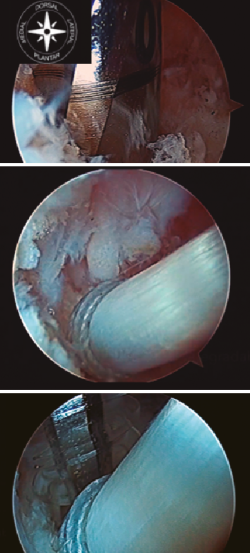

Figura 1. Identificación, desbridamiento y tracción con vessel loop del tendón flexor hallucis longus (FHL). A: FHL; B: astrágalo; C: calcáneo.

Una vez identificado el FHL, es importante realizar un correcto desbridamiento del túnel osteofibroso por donde discurre, para así poder obtener la mayor cantidad posible del mismo. Recomendamos dar una sutura en el tendón FHL, o alternativamente usar una pinza artroscópica, para traccionar del mismo y así poder obtener tendón FHL incluso de zona 2 (Figura 1).

Figura 2. Tracción del tendón flexor hallucis longus (FHL) y sección del mismo en la zona 2, con flexión de la primera metatarsofalángica y tobillo.

La longitud mínima ideal del tendón FHL para la transposición en el calcáneo es de 15 mm. Cuando se realiza el corte del FHL con la tijera artroscópica, se debe flexionar el tobillo y la primera metatarsofalángica para obtener la máxima longitud posible y a su vez proteger el paquete neurovascular (Figura 2).

Una vez seccionado el tendón, se saca a través del portal posteromedial y se realiza una sutura de refuerzo de tipo Krakow y medimos el tamaño de la plastia (Figura 3).

Figura 3. Obtenemos la plastia por el portal posteromedial, se realiza sutura de refuerzo de tipo Krackow y medición de la plastia.

Figura 4. Túnel ciego en la tuberosidad posterior del calcáneo. Introducción de la plastia y fijación con tornillo de biotenodesis.

Como mínimo, se debe introducir de 10 a 15 mm de la plastia obtenida. Una vez realizado el túnel, se introduce una sutura en el ojal de la aguja de Kirschner y traccionamos de la aguja desde plantar para poder pasar las suturas a través del túnel labrado y así poder introducir el tendón en el interior del túnel. Posteriormente, con el tobillo en flexión plantar, se tracciona de las suturas para tensar el tendón del FHL bajo visión artroscópica directa, con el fin de obtener una tensión adecuada de la plastia, y se fija con un tornillo de biotenodesis del mismo tamaño o 1 mm más ancho que el túnel del calcáneo realizado (Figura 4).